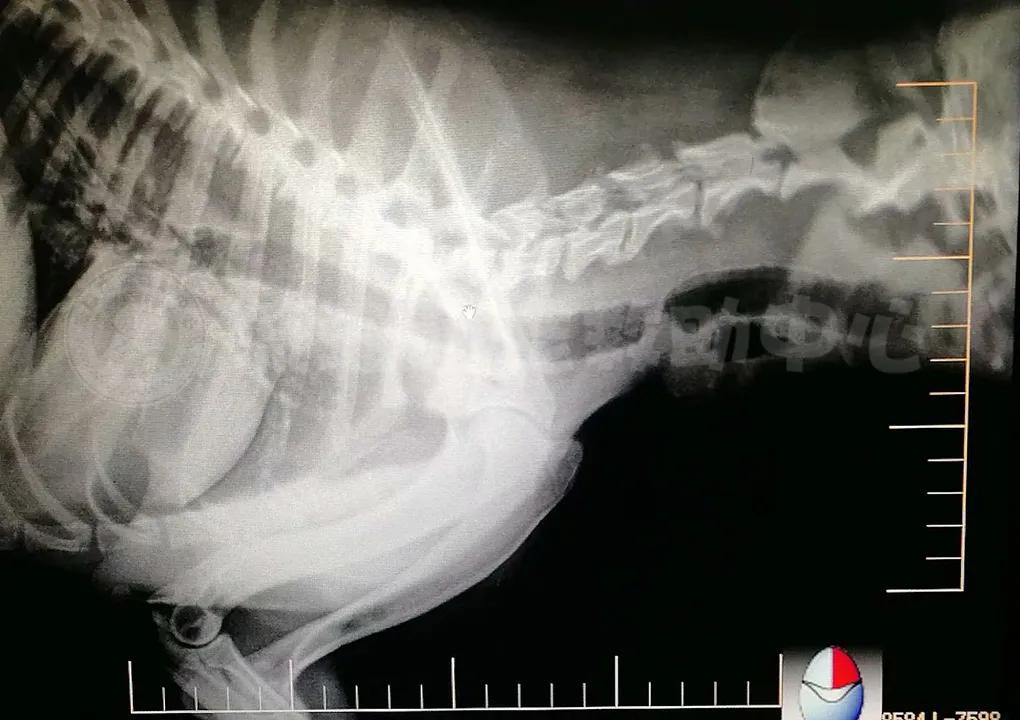

△大耳朵比格的CT照

大概名字果然有种魔法吧,让拥有新名字大耳朵和人世间重新有了牵绊,更因为杨阿姨的不放弃,志愿者的援手,医生的精准治疗,让这只曾被人抛弃又被人割喉伤害的狗狗,拥有了另一种狗生。